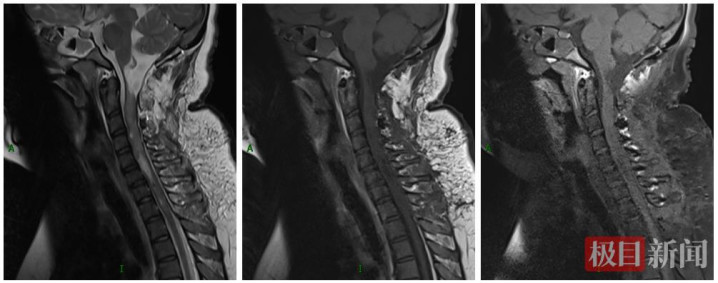

术后MRI显示,病灶完整切除,正常延髓受压菲薄